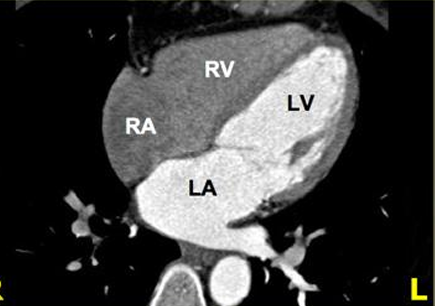

Cardiac CT Scan

Also known as Coronary CT Angiography (CCTA)

Coronary CT Angiography (CCTA)

Cardiac CT Scan (9)

Evaluating the anatomy and function of the heart chambers

Diagnosing a variety of cardiovascular disorders